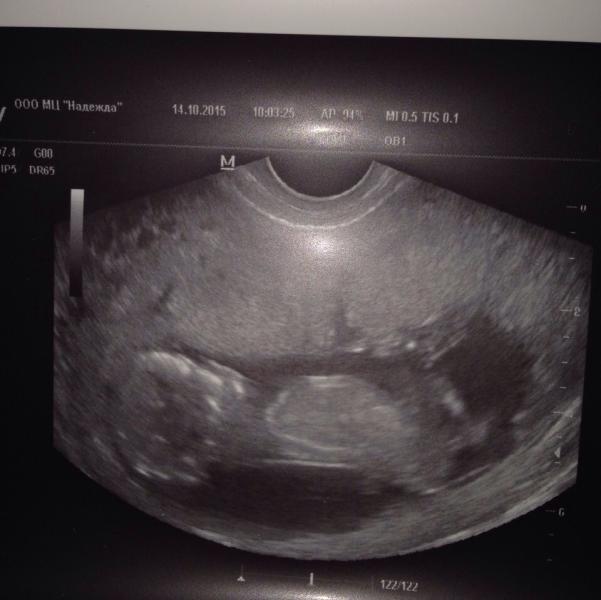

Первый скрининг! По узи сказали все хорошо у нас .. И у нас будет сыночек) ☺️

@pushkina, мне внутренним датчиком делали .. И прям со стороны попы писюн торчал.. Муж сразу увидел .. И она - "вот ваш писюн "

@alya544, мне в 12,5 сказали мальчик😊 к 13ти полным неделям вполне могут пол увидеть. На втором скрининге пол подтвердили. В заключении написано Плод мужского пола😆